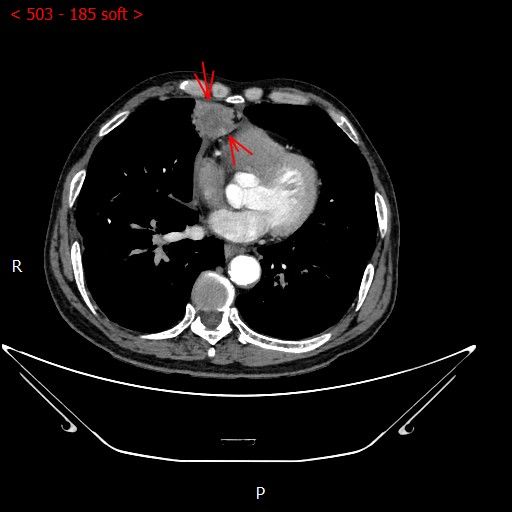

术前影像

男性患者,68岁,检查发现右肺中叶肿块,大小约3.5cm×2.4cm,因患者有慢性支气管炎、肺气肿、肺大泡,基础病较多,无法耐受常规外科手术治疗;经与患者本人及家属多次沟通。血管介入科团队根据患者具体情况决定对该患者施行CT引导下肺肿瘤射频消融术。经全科术前讨论:肿瘤位置毗邻心脏、纵膈、胸膜多处重要器官,手术要求穿刺精准,消融位置精确,尽量避免恶性心率失常,心脏包膜、胸膜、纵膈损伤。经过前期的精心术前准备,2023年7月18日,在血管介入科团队和CT室默契配合下,此次射频消融手术顺利完成。手术全过程仅用时约40分钟,其中消融时间约5分钟。CT观察下见肿瘤形变,周围肺组织呈现“晕”征,提示本次消融范围基本覆盖全肿瘤。术中患者无疼痛并且未产生并发症。本次手术达到杀死肿瘤细胞的同时,最大限度的减少创伤、保留肺组织。